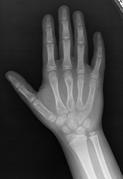

Normal hand RA - Damaged finger joints RA - Fused finger joint

Normal hand bones RA - Damaged hand bones RA - Damaged hand

Description           English: Projectional radiography ("X-ray") of a normal hand of a 8 year

old male, by dorsoplantar view.